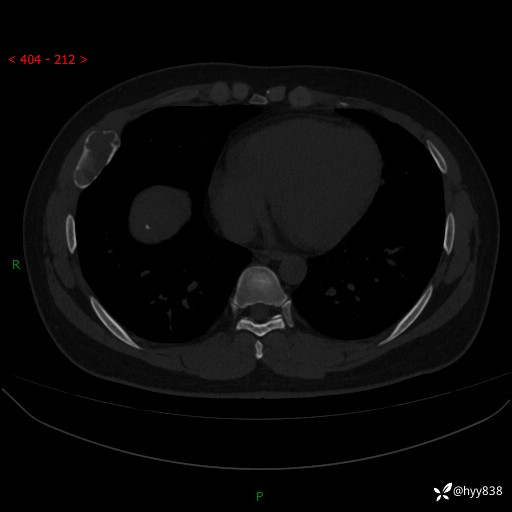

年轻小伙,右侧胸部疼痛4天余。病理科说肯定不是骨纤,那是啥---结果公布~

性别:男

年龄:24岁

主诉:右侧胸部疼痛4天余。

现病史:患者约4天前突发右侧胸部疼痛,无瘙痒,无头痛、头晕,无心慌、胸闷、呼吸困难、咳嗽、咳痰、咯血,无腹痛、腹胀等不适,未作进一步诊治。于2024年5月外院行胸部CT平扫示右侧肋骨骨质改变。现为求进一步治疗,遂于我院就诊。门诊以“胸壁肿物”收入我科。 患者自起病以来,精神可,睡眠可,饮食可,大小便正常,体重无明显改变。

胸部CT平扫